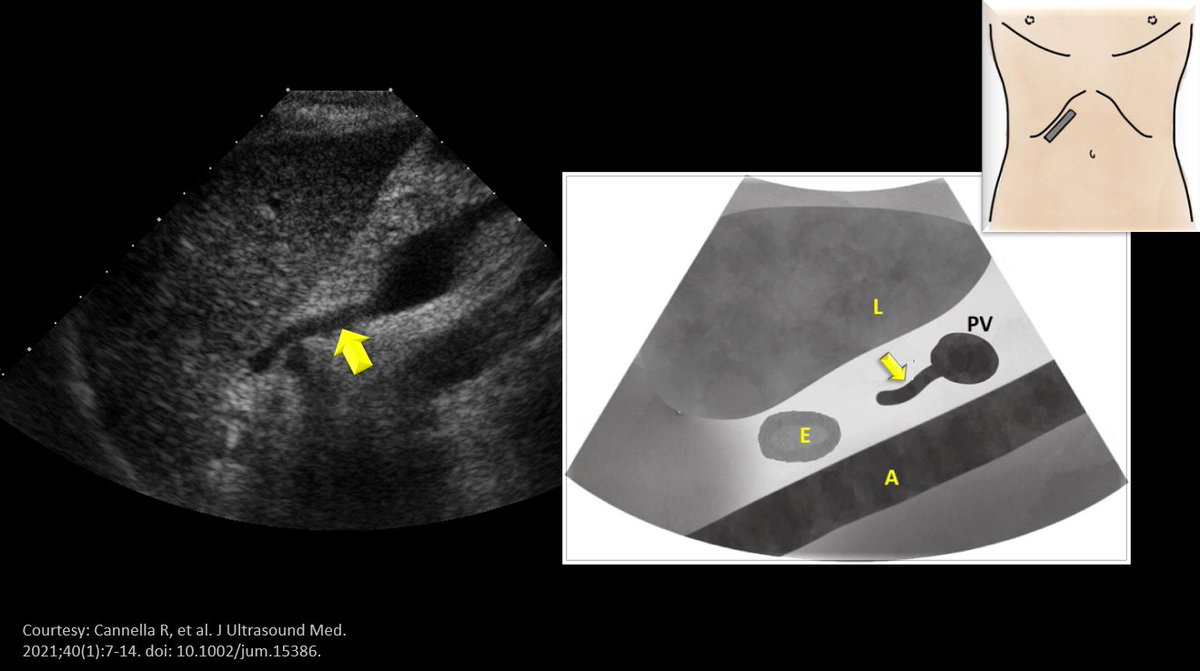

#POCUS quiz: What is the structure indicated by arrow? Corresponding illustration as well as scan position shown. #Anatomy exercise for #VExUS enthusiasts. #MedEd Poll in thread 👇 (L = liver, PV = portal vein, E = esophagus, A = aorta)

(L = liver, PV = portal vein, E = esophagus, A = aorta)